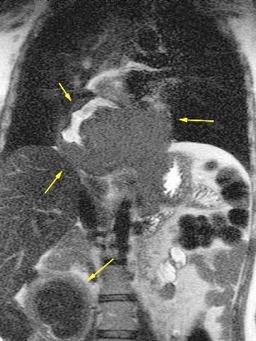

T. mixto de células

Ganglios retroperitoneales (flechas negras)

germinales del testículo izquierdo Nódulos pulmonares múltiples. (flechas verdes). Ganglios paratraqueales. (flechas amarillas). Dudoso ensanchamiento retrocrural (flechas negras)

Panda A et al. “Straddling Across Boundaries”. Thoracoabdominal Lesions: Spectrum and Pattern Approach. Curr Probl Diagn Radiol, 2015